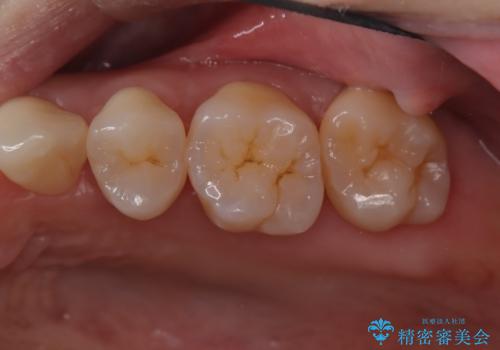

- 定期的にクリーニング(保険適応)に通って頂いている患者さんです。歯周ポケットが4ミリあったため歯茎を開いて歯石を除去するためにオープンフラップ術を行うことにしました。

歯周ポケットがそれほど深くない患者さんでしたが、いざ歯茎を開いてみるとそこにはたくさんの歯石がありました。もし歯周ポケットが4ミリだからと言って放置していれば数年後には、沢山の骨が無くなっていたことが予期出来ます。現段階で歯茎の下にある歯石を除去することにより骨が無くなることを予防する事が出来ました。